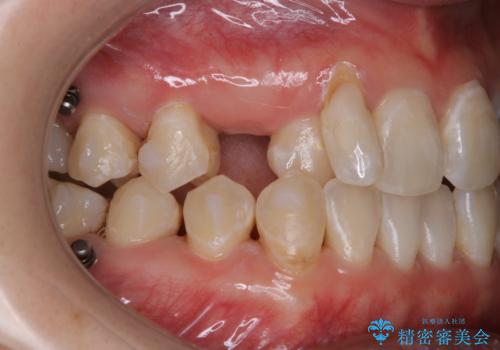

インビザライン矯正中にPMTCでコーヒーによるステインの除去

- コーヒーを毎日頻繁に飲むため、ステインがついてしまうとのことでした。全体的に頑固なステインの付着が見られたため、PMTC60分コースを行いました。

PMTC(保険外治療)は、毎日の歯磨きで落としきれない汚れや、コーヒ、紅茶・タバコのヤニなどの着色も除去します。目には見えない歯と歯の間・歯肉の境目・インビザライン中はアタッチメント周囲などに残っているプラーク(歯垢)もしっかり取り除きます。PMTCでは専門的な機械や材料を使用して、徹底的に汚れを除去するため、虫歯・歯周病・口臭予防などにつながります。